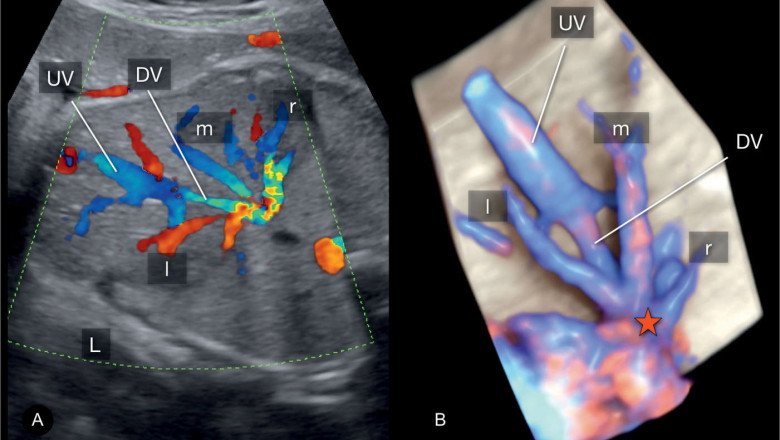

A Doppler ultrasonography is used to assess blood flow. Physicians utilize the findings to identify whether a blood artery is blocked, narrowed, or leaking. Doppler Ultrasound are used by healthcare practitioners to check internal tissues such as bones and organs. A Doppler ultrasonography is used to assess how well blood flows through the veins and arteries.